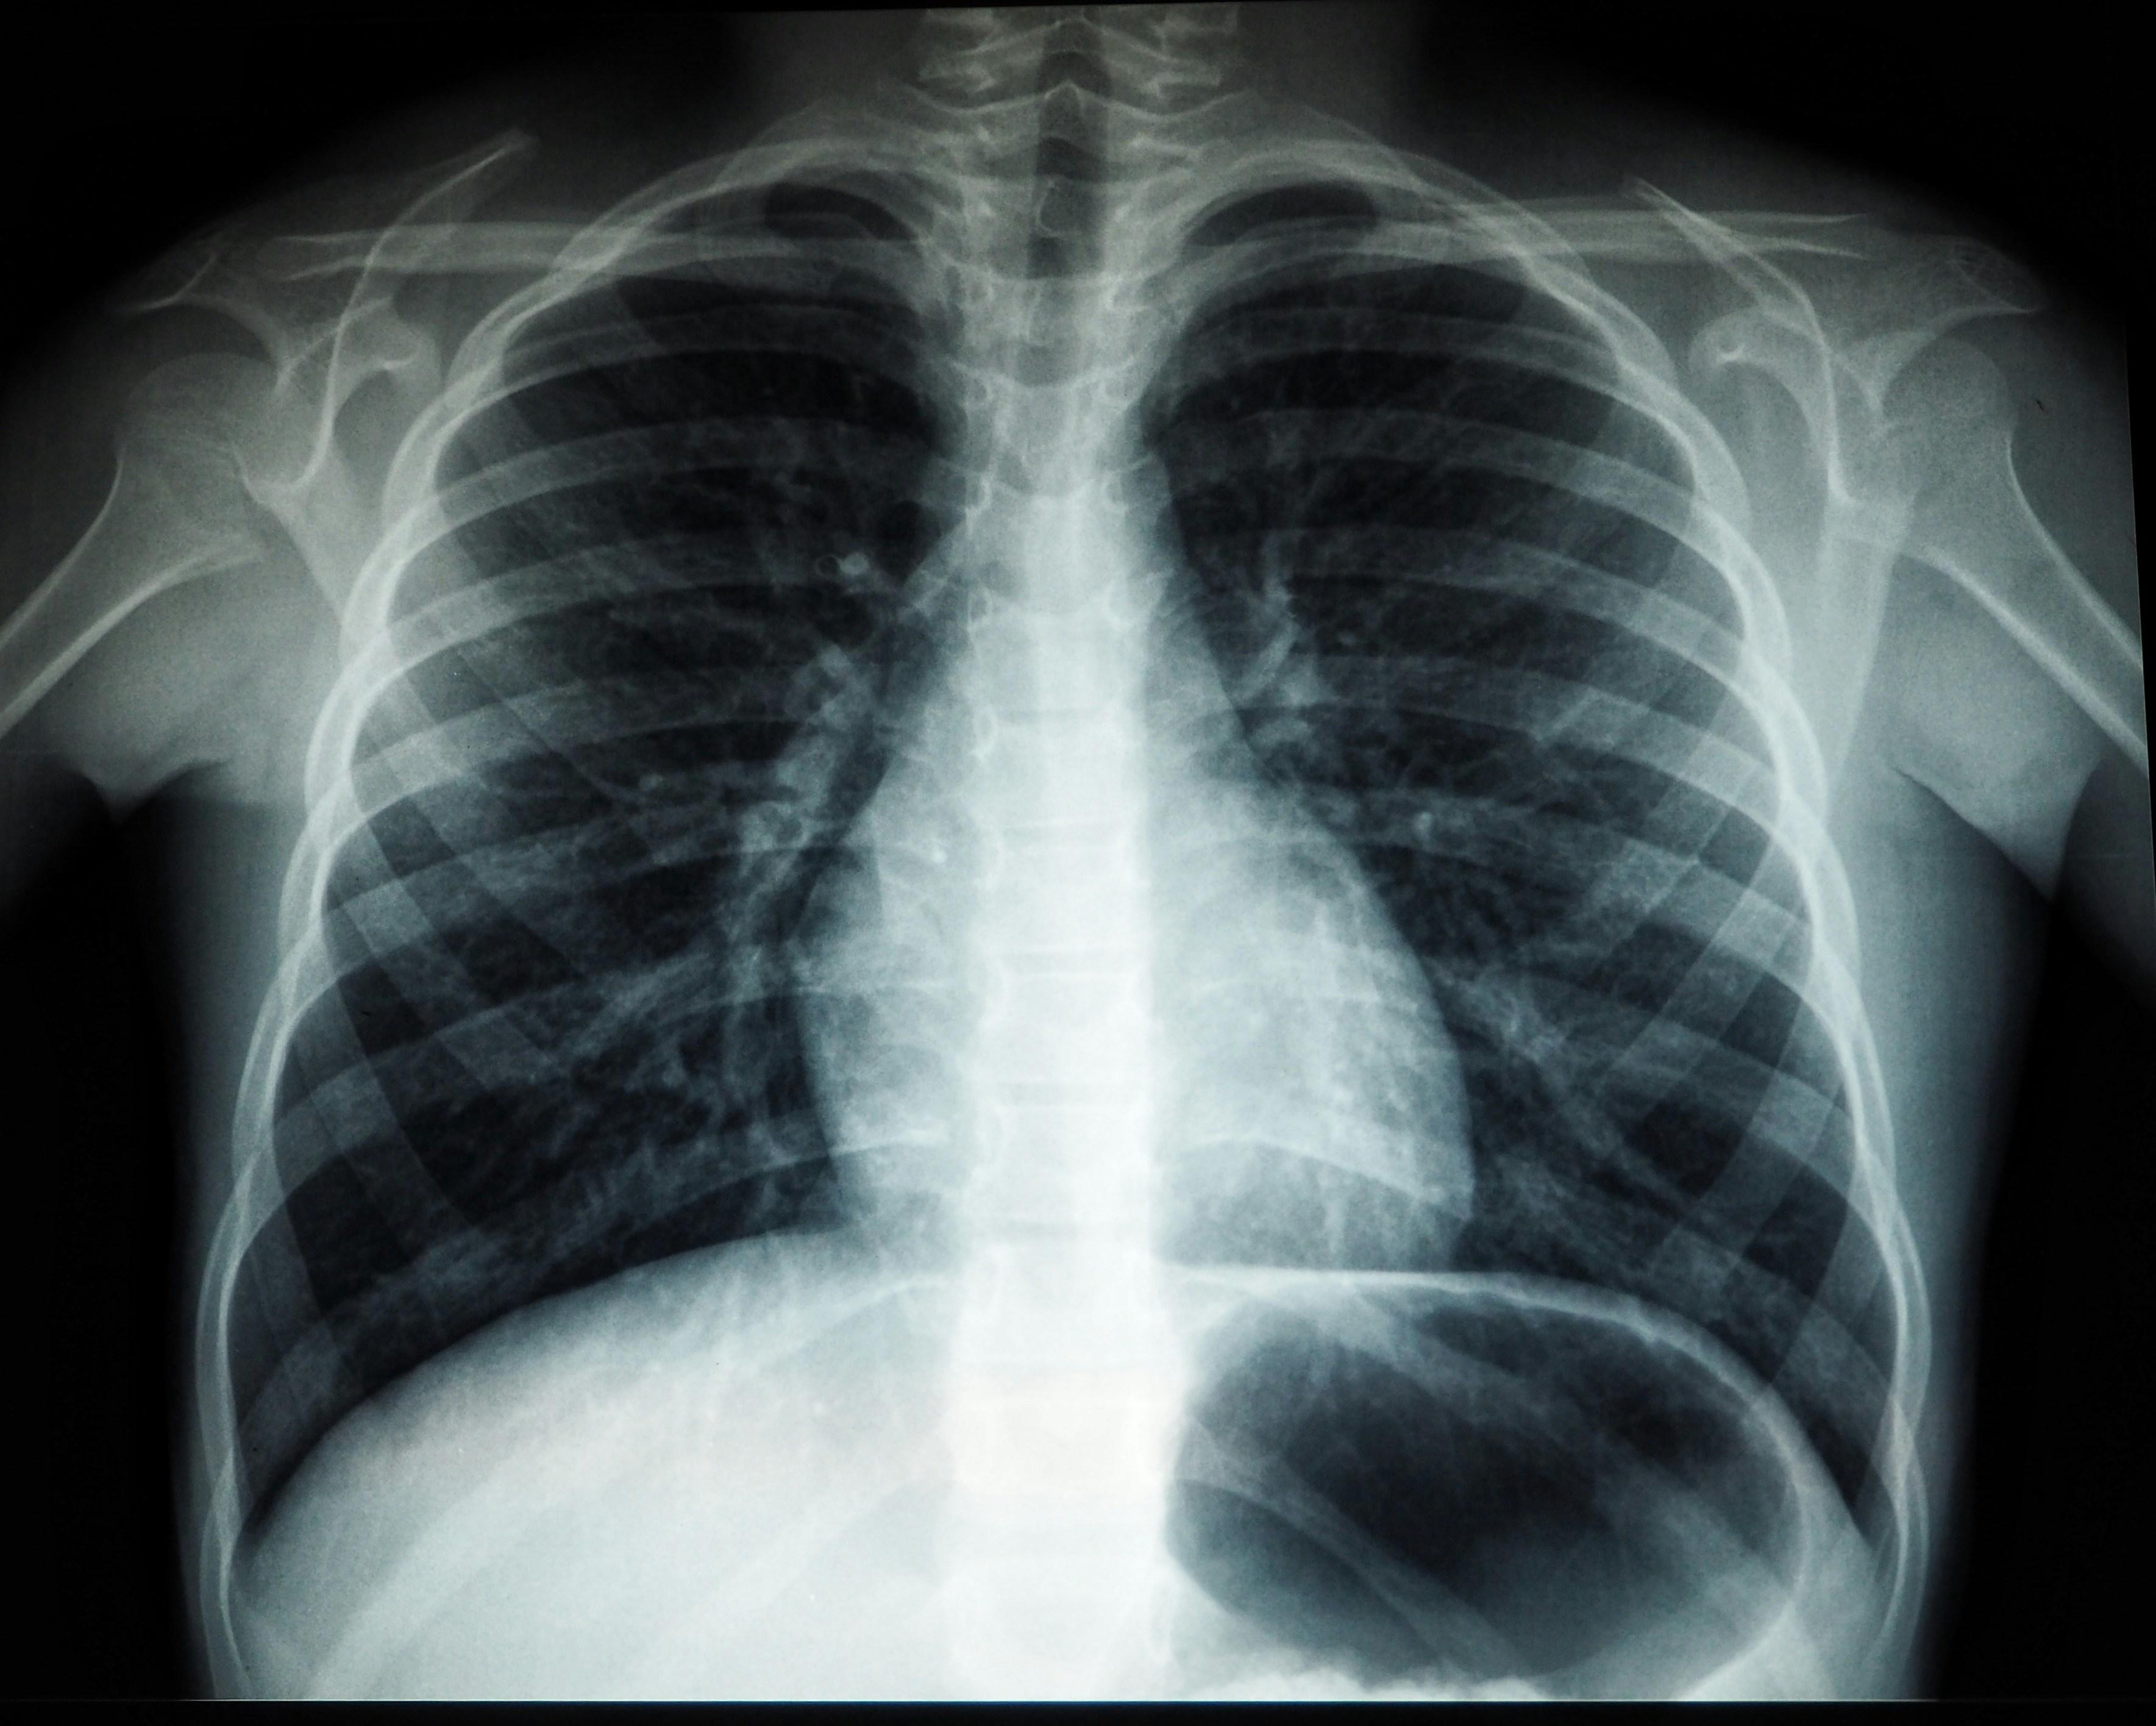

World Tuberculosis Day: Photo: Unsplash

हर साल 24 मार्च को वर्ल्ड ट्यूबरक्लोसिस डे मनाया जाता है, ताकि लोगों को इस गंभीर संक्रामक बीमारी के प्रति जागरूक किया जा सके. भारत में टीबी आज भी एक बड़ी स्वास्थ्य समस्या बनी हुई है और दुनिया में सबसे ज्यादा मामले यहीं दर्ज किए जाते हैं. डॉक्टरों के मुताबिक, सही समय पर लक्षण पहचानकर और पूरा इलाज लेकर इस बीमारी को पूरी तरह ठीक किया जा सकता है.